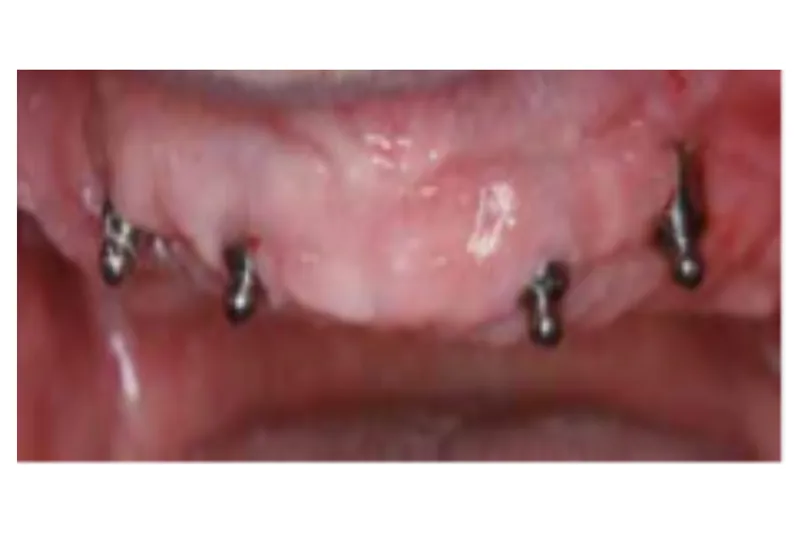

Det er imidlertid ikke alle tandløse patienter, der har tilstrækkeligt med knoglevolumen eller økonomi til at få fremstillet implantat-understøttede broer, men undersøgelser viser, at også implantatunderstøttede dækproteser kan hjælpe mange patienter.

Antallet af indsatte implantater kan reduceres, og det bliver enklere for patienter at udføre hygiejne omkring implantatdelene. Dette er væsentligt for mange ældre patienter og ikke mindst for geriatriske patienter, hvor man på et tidspunkt kan blive nødsaget til at forsimple behandlinger – ”backing off”, efterhånden som patienter bliver mindre i stand til selv at renholde tanderstatningsdelene.